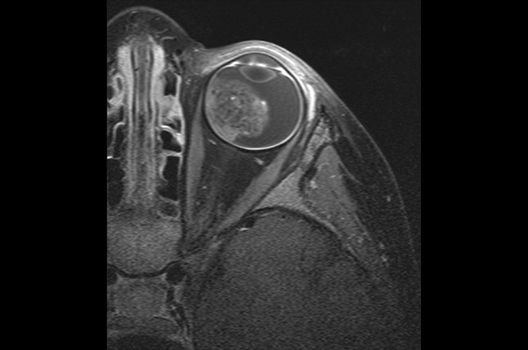

Die Magnetresonanztomographie (MRT) ist ein Verfahren, bei dem durch magnetische Kräfte Bilder des Körperinneren angefertigt werden. In der Neuroradiologie können manchmal kleinste Veränderungen schwere Folgen haben; daher forschen wir an der Entwicklung hochauflösender MRT-Sequenzen, mit denen diese Prozesse und auch einzelne Nervenfaserbahnen sichtbar gemacht werden können. Darüber hinaus sind bei vielen Erkrankungen des Gehirns die Blutgefäße betroffen. Daher arbeiten wir an der Neu- und Weiterentwicklung von MRT-Sequenzen zur Darstellung der Blutgefäße und zur Blutflussanalyse (sog. „Angio-MRT“). Einen besonderen Forschungsschwerpunkt unserer Klinik stellen die MR-Protonenspektroskopie und die funktionelle MRT dar, mit denen die Analyse einzelner chemischer Substanzen im Hirngewebe oder die Darstellung ausgewählter Hirnfunktionen möglich ist.